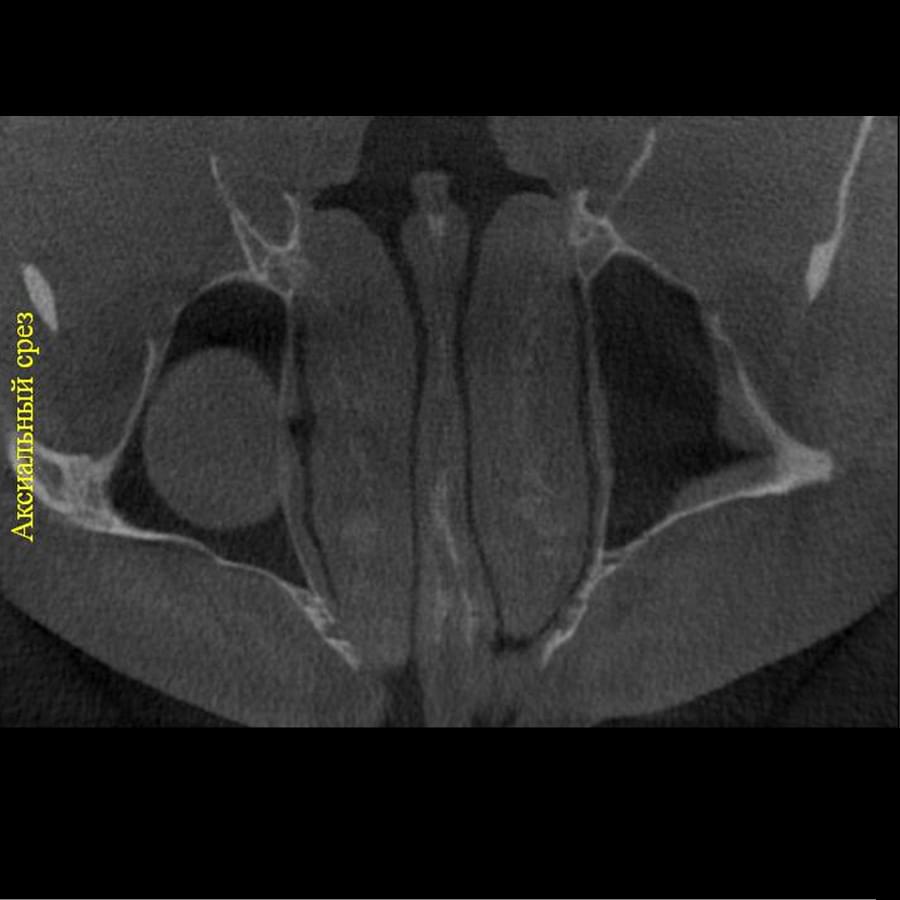

Комп'ютерна томографія

Щелепно-лицева діагностика

Ми використовуємо найсучасніше обладнання відомого виробника PLANMECA, що дозволяє отримувати високоякісні зображення за короткий час. Крім того, ми маємо власний сервер, на якому створюємо окрему скриньку для кожного лікаря, що забезпечує максимальну зручність та ефективність роботи.